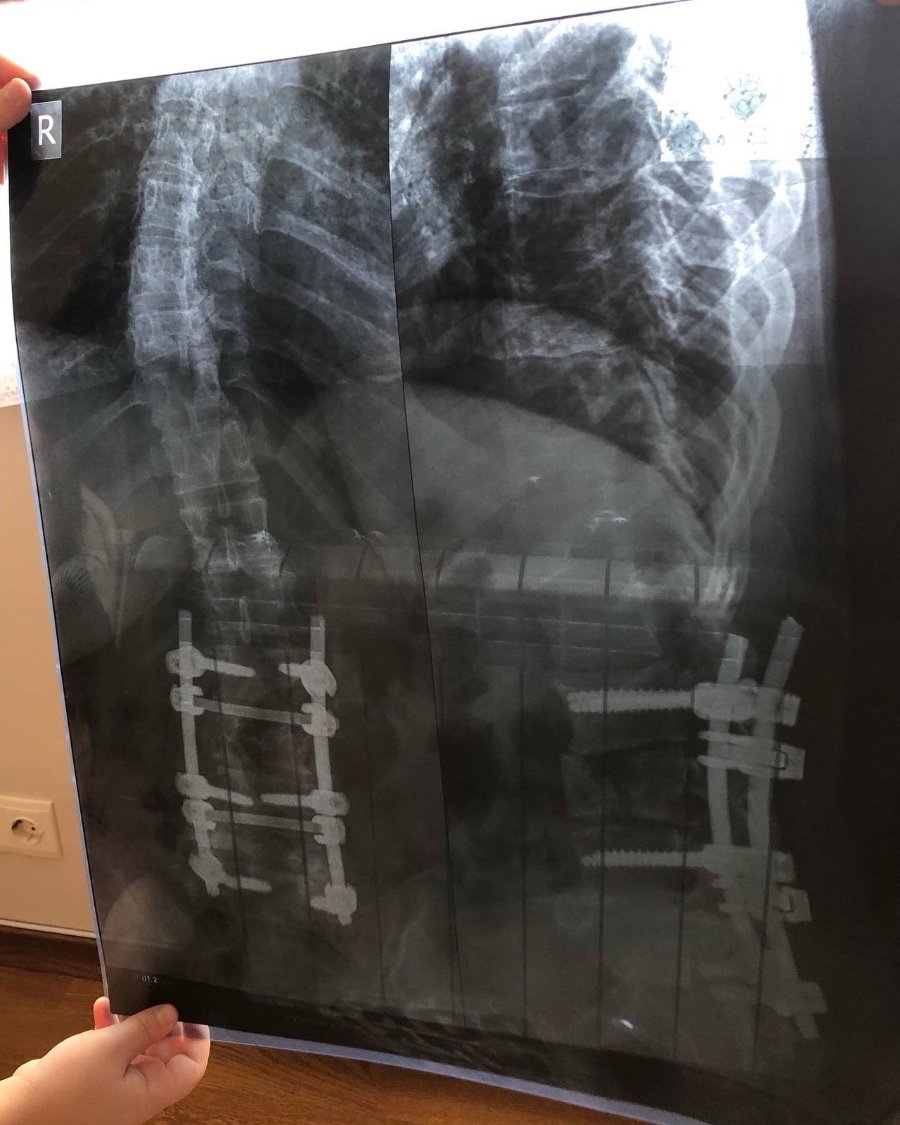

Зараз пластини, які підтримували опорно-рухову діяльність жінки, зламались і потрібна операція. Орієновна вартість операції – 300 тисяч гривень. Операцію планують в Київській обласній клінічній лікарні в Міжнародному центрі нейрохірургії.